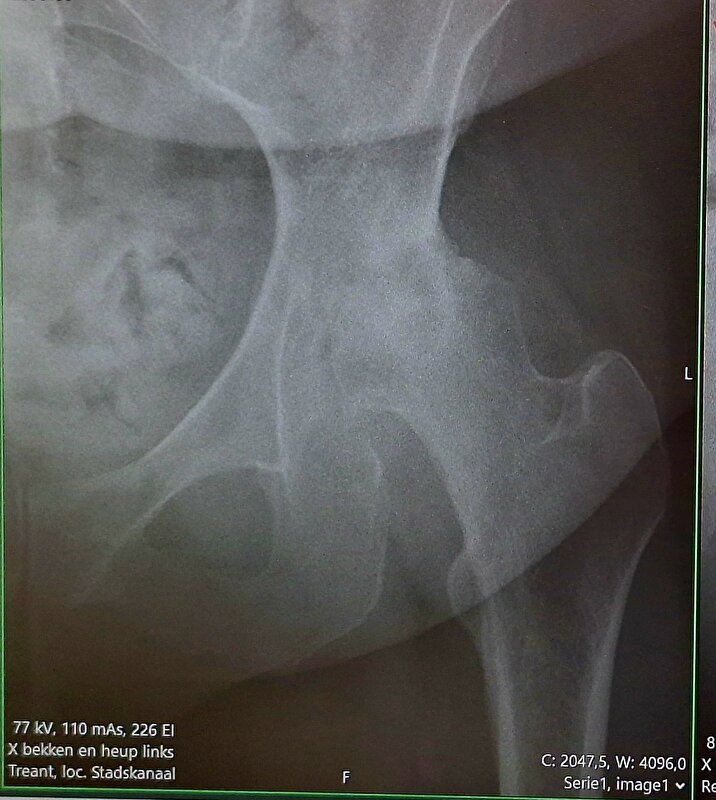

Ik heb een foto gemaakt van de röntgen-foto.. hierop zie je dat er geen kraakbeen meer zit tussen mijn heupkop en heupkom. Normaal loopt daar een licht gekleurd ljntje/randje tussendoor en bij mij lijkt het wel 1 geheel. Dat is dus bot op bot. Ook is mijn heupkop al vervormd en niet meer mooi rond. Omdat ik al zoveel been-pijn ben gewend kan ik niet herkennen welke pijn nu door mijn heup komt en welke vanuit mijn rug (uitstraling) maar volgens de orthopeed moeten veel klachten wel door die heup komen.

Afbeelding

Idd daar zit niks meer tussen.